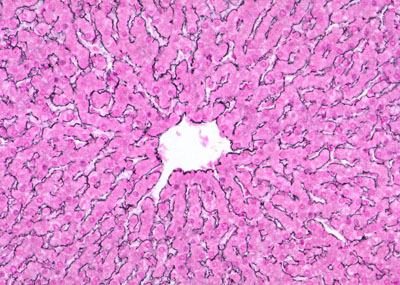

HÍGADO

La técnica de Carmín de Best nos ayuda a identificar las inclusiones de glucógeno en los hepatocitos.Hígado de mamífero, observe la disposición del lobulillo clásico.Los hepatocitos se organizan en cordones alrededor de las venas centrales.Identifique los elementos de la triada portal hepática.Observe las fibras reticulares que conforman el parénquima del hígado. Imagen de la Universidad de Yale.Es posible observar canalículos biliares en los bordes de los hepatocitos.Las regiones que se observan «en blanco» junto con los eritrocitos son los sinusoides que irrigan el hígado.Aquí se observan varios sinusoides hepáticos.Los hepatocitos maduros suelen ser binucleados.Identifique el arreglo cordonal de los hepatocitos alrededor de la vénula central.